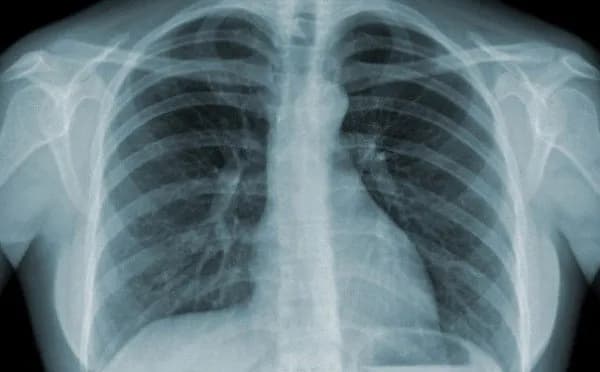

- X-quang ngực: Phim chụp X-quang có thể cho thấy hình ảnh tổn thương phế nang lan tỏa ở cả hai bên phổi, có xu hướng tiến triển nặng dần.